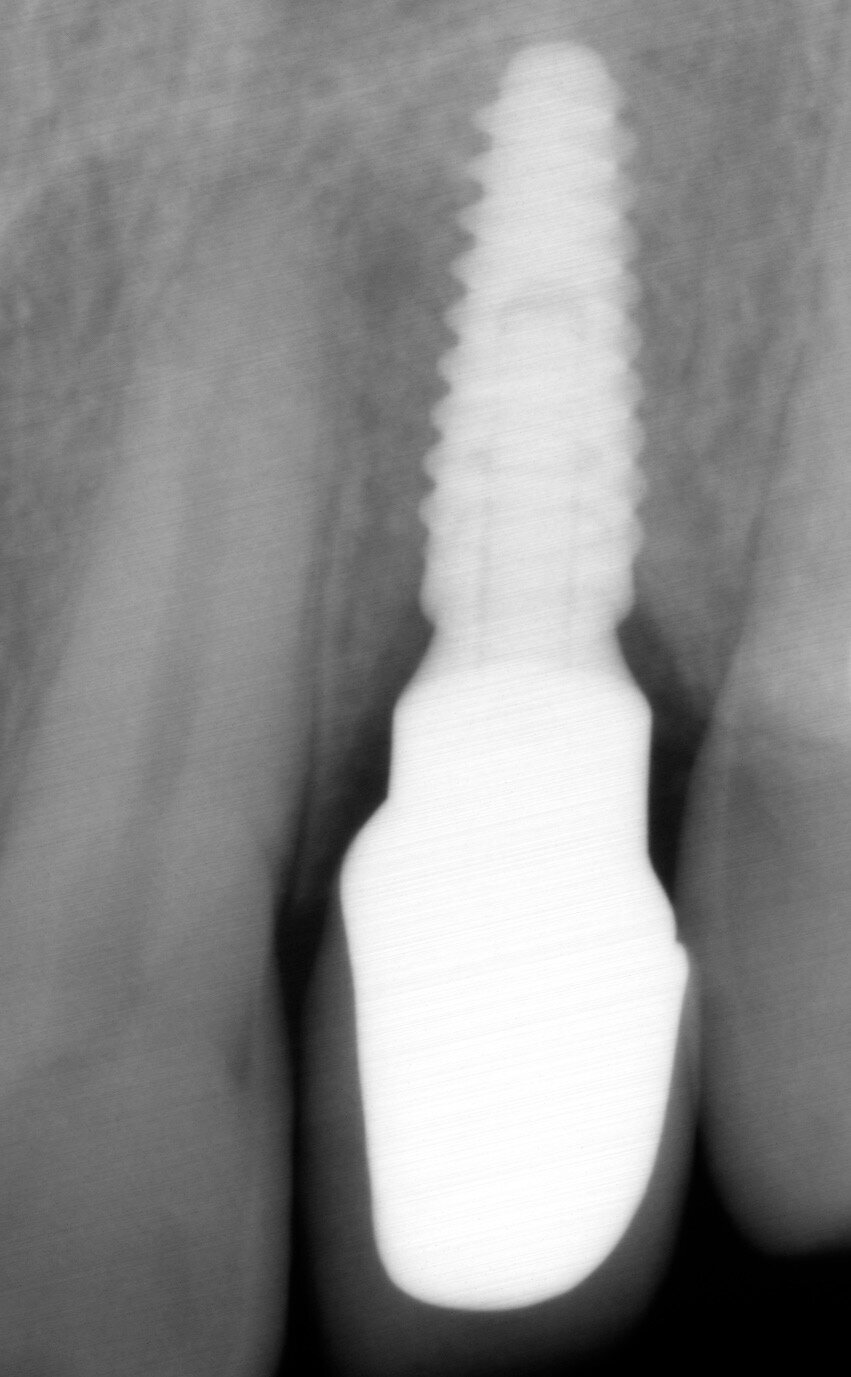

Six months after the primary socket preservation technique, an implant was placed (Figs. 7 & 8) and an immediate provisional restoration was placed. Four months later, the definitive screw-retained crown was placed (Figs. 9 & 10). The five-month postoperative periapical radiograph showed a good bone level around the implant (Fig. 11).

Fig. 7: Radiograph after placement of the implant, showing the stable socket bone site.

Fig. 11: Periapical radiograph taken five months after placement of the definitive restoration. Note the amount of peri-implant marginal bone that was preserved.